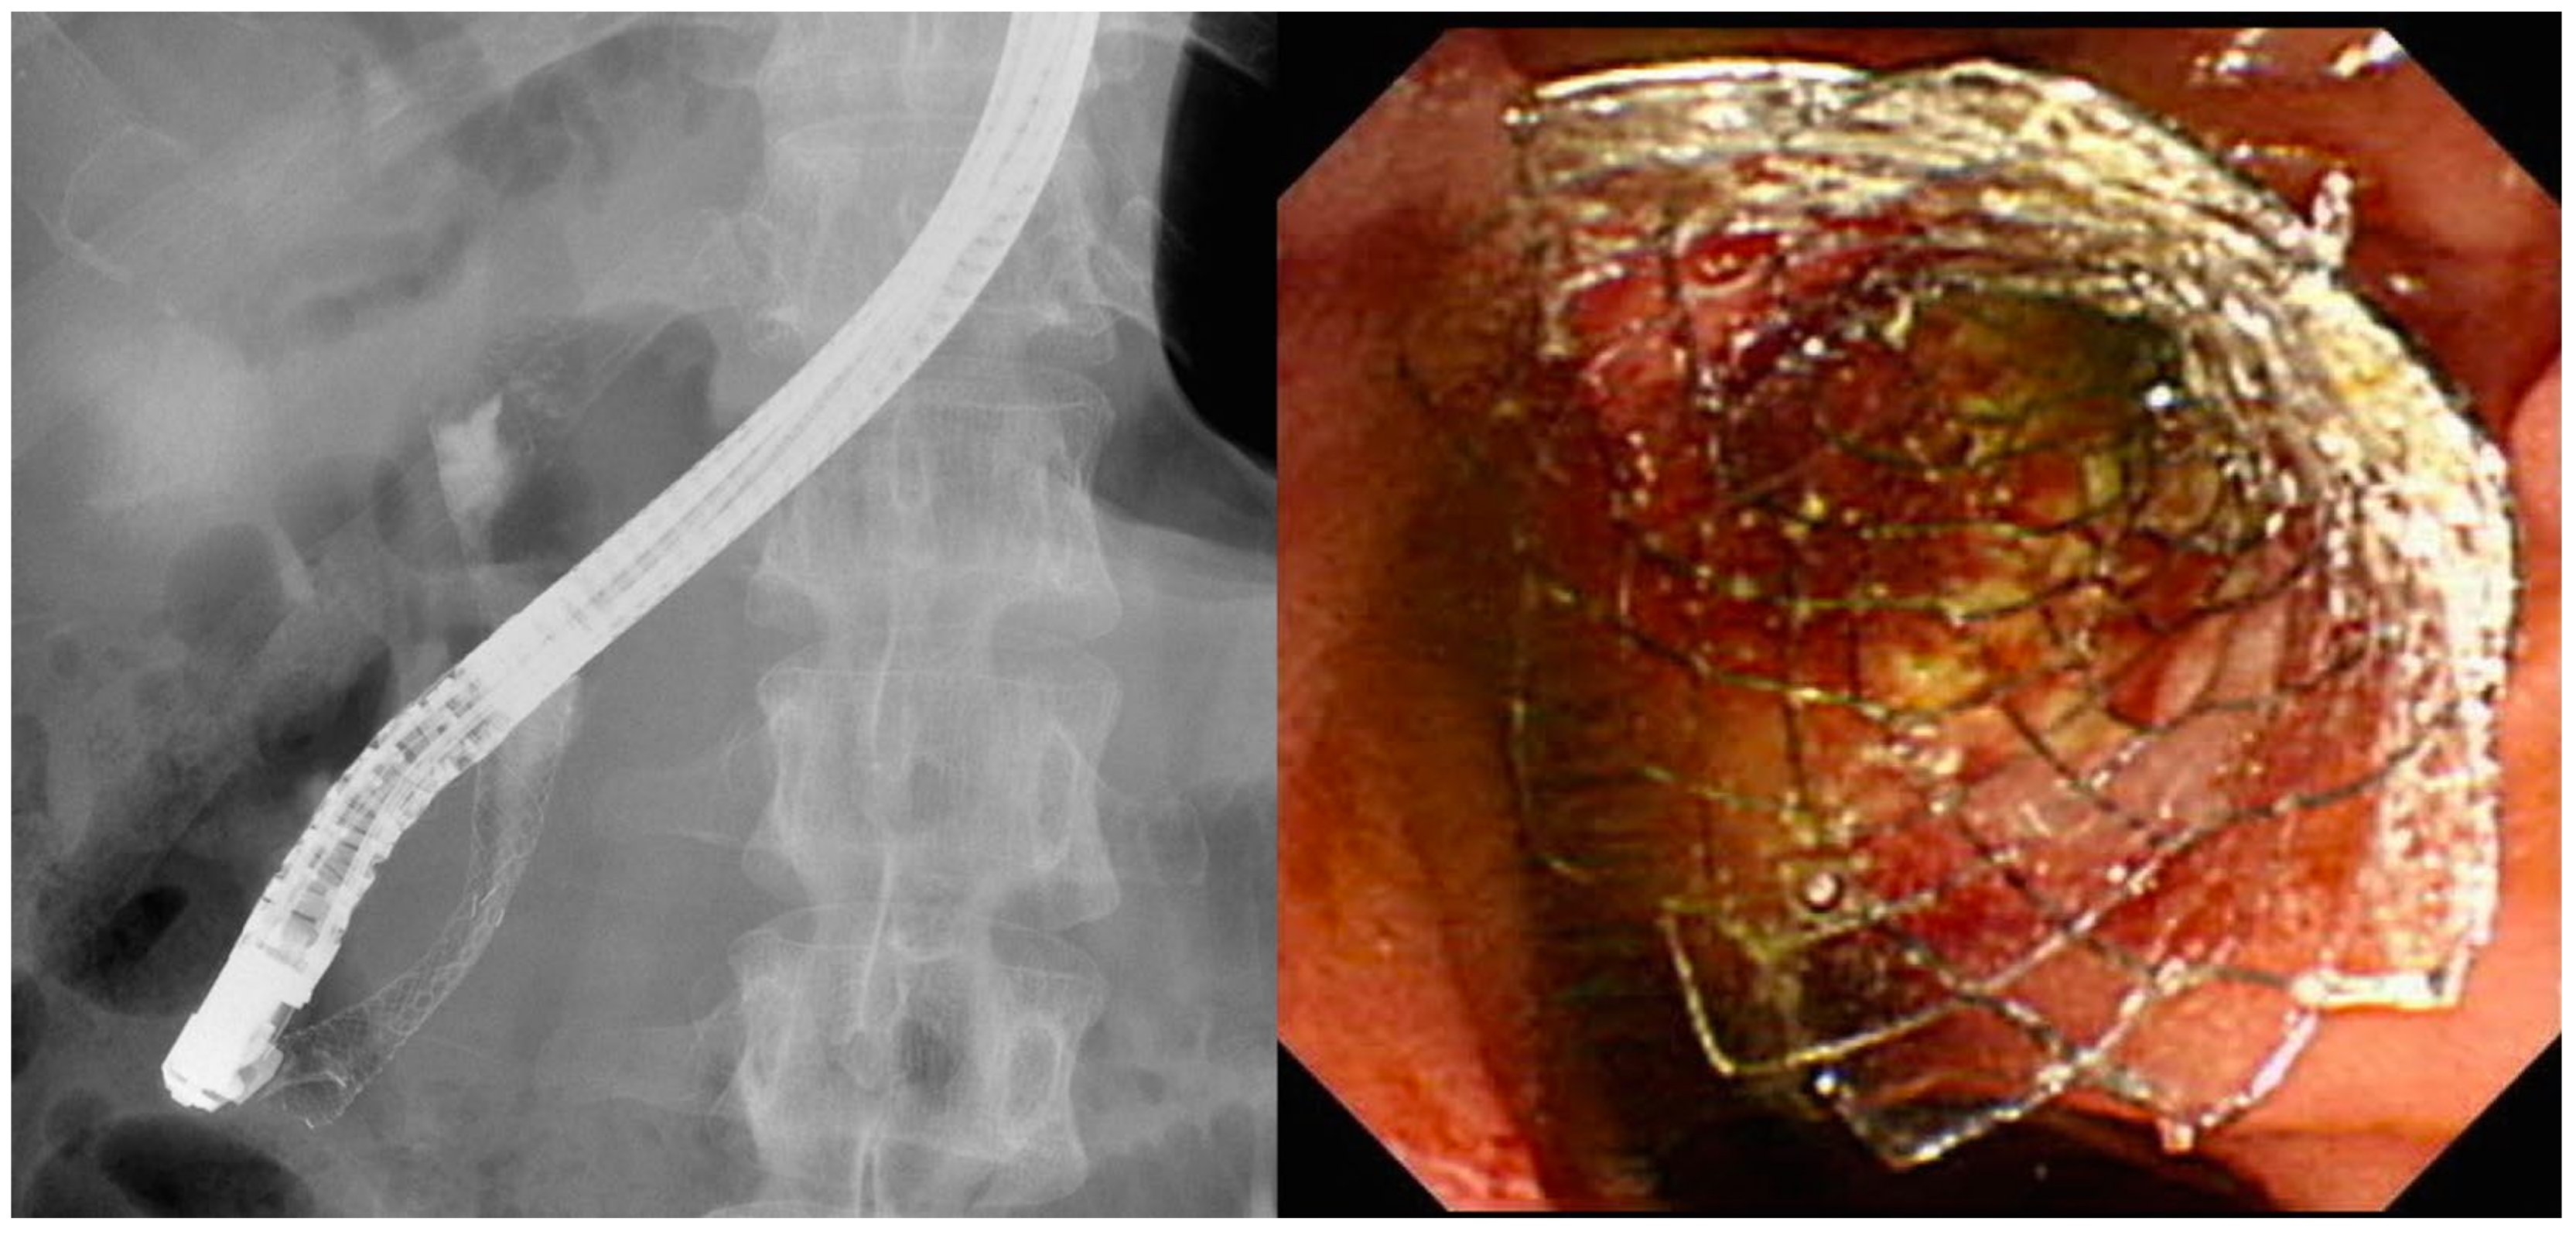

4.2. Stent Selection

- Chahal, P.; Baron, T.H. Expandable metal stents for endoscopic bilateral stent-within-stent placement for malignant hilar biliary obstruction. Gastrointest. Endosc. 2010, 71, 195–199. [Google Scholar] [CrossRef] [PubMed]

- Kogure, H.; Isayama, H.; Kawakubo, K.; Sasaki, T.; Yamamoto, N.; Hirano, K.; Sasahira, N.; Tsujino, T.; Tada, M.; Koike, K. Endoscopic bilateral metallic stenting for malignant hilar obstruction using newly designed stents. J. Hepatobiliary Pancreat. Sci. 2011, 18, 653–657. [Google Scholar] [CrossRef]

- Hwang, J.C.; Kim, J.H.; Lim, S.G.; Kim, S.S.; Yoo, B.M.; Cho, S.W. Y-shaped endoscopic bilateral metal stent placement for malignant hilar biliary obstruction: Prospective long-term study. Scand. J. Gastroenterol. 2011, 46, 326–332. [Google Scholar] [CrossRef]

- Kogure, H.; Isayama, H.; Nakai, Y.; Tsujino, T.; Ito, Y.; Yamamoto, K.; Mizuno, S.; Yagioka, H.; Kawakubo, K.; Sasaki, T.; et al. Newly designed large cell Niti-S stent for malignant hilar biliary obstruction: A pilot study. Surg. Endosc. 2011, 25, 463–467. [Google Scholar] [CrossRef]

- Saleem, A.; Baron, T.H.; Gostout, C.J. Large-diameter therapeutic channel duodenoscope to facilitate simultaneous deployment of side-by-side self-expandable metal stents in hilar cholangiocarcinoma. Gastrointest. Endosc. 2010, 72, 628–631. [Google Scholar] [CrossRef]

- Park, D.H.; Lee, S.S.; Moon, J.H.; Choi, H.J.; Cha, S.W.; Kim, J.H.; Seo, D.W.; Lee, S.K.; Park, S.H.; Lee, M.S.; et al. Newly designed stent for endoscopic bilateral stent-in-stent placement of metallic stents in patients with malignant hilar biliary strictures: Multicenter prospective feasibility study (with videos). Gastrointest. Endosc. 2009, 69, 1357–1360. [Google Scholar] [CrossRef]